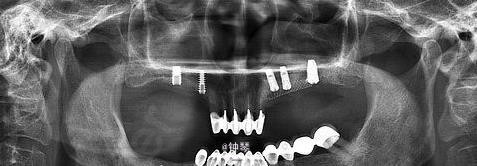

随访 讨论

种植体良好。